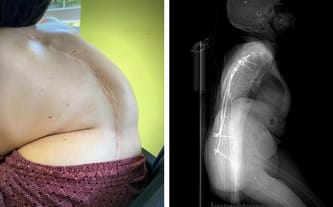

Obecnie moje lewe biodro wbija mi się w żebra mocno je deformując. Są sprasowane w szpic i odstają tak mocno, że nie mogę leżeć na brzuchu, bo mam wtedy wrażenie łamanych żeber. Nie dość, że moje lewe płuco jest przez to ściśnięte, przez co mam utrudnione oddychanie, to dodatkowo skolioza przeszkadza mi w utrzymywaniu pionu podczas siedzenia. Cała jestem wygięta i trudniej jest mi przez to utrzymać głowę bez podpierania. Rdzeniowy zanik mięśni zabrał mi możliwość chodzenia, a przez skoliozę siedzenie jest coraz trudniejsze i wymaga ode mnie coraz więcej energii, której nie mam. Dawno już straciłam nadzieję, że może być lepiej.

Zdążyłam już spisać się na straty, ale w ostatnim czasie w końcu pojawiła się nadzieja, która stała się dla mnie światełkiem w tunelu. Skontaktowałam się ze znanym specjalistą – Pawłem Nosarzewskim, który zakwalifikował mnie do operacji, która może zmniejszyć moje skrzywienie do 40 lub nawet 30 stopni, czyli o ponad połowę!